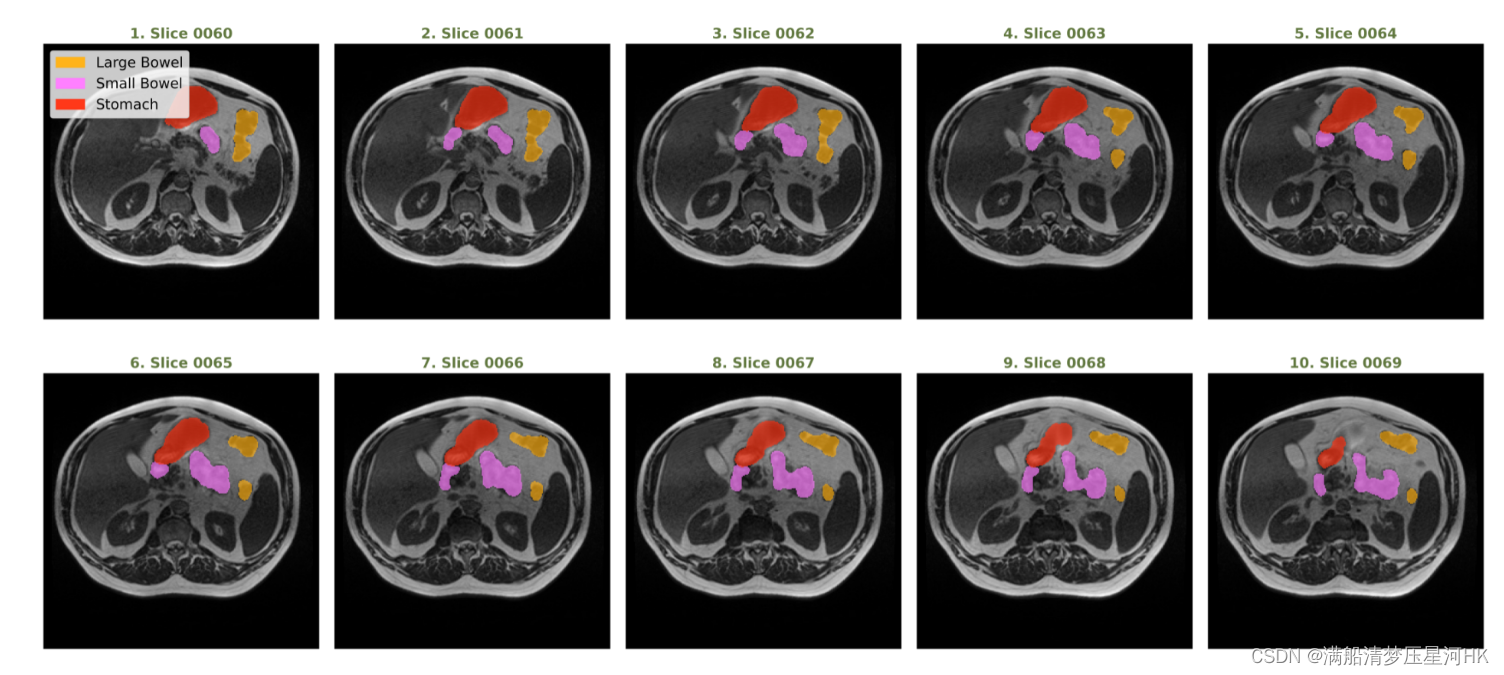

可视化图片和mask(单通道原图)

病例18,day0,切片0060-0069的图片和mask标签可视化长这样: